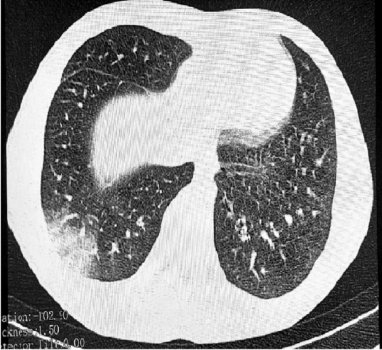

EVALI представляет серьезную угрозу для здоровья. При этом заболевании происходит воспаление и рубцевание бронхиол – мельчайших разветвлений дыхательных путей. В результате поражения дыхательной системы при дыхании может появляться характерный звук, напоминающий лопающийся попкорн, из-за чего болезнь также получила неофициальное название "попкорновая".

Медики отмечают, что эффективного лечения от данного заболевания в настоящее время не существует. Случаи EVALI широко регистрировались в США с 2019 года и связывались с использованием электронных сигарет и вейпов.